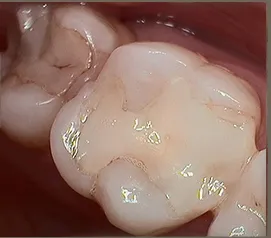

This patient needed a crown on a sensitive tooth and walked out with the final crown in under 2 hours!!